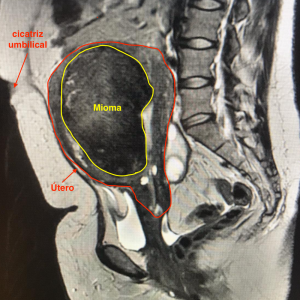

Ressonância magnética após embolização uterina demonstrando importante redução das dimensões do útero e do mioma